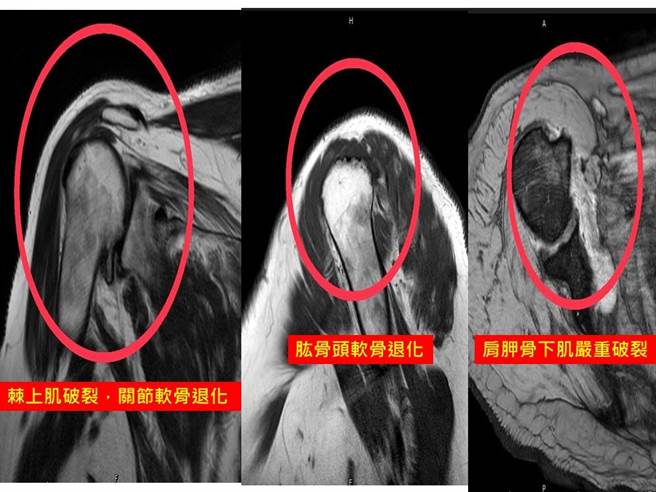

86岁江先生右肩旋转肌近年退化破裂,不仅手臂无法举高且「一动就痛」,连睡觉也时常痛醒,多年来严重影响生活品质。(大里仁爱医院提供/潘虹恩台中传真)

86岁江先生右肩旋转肌近年退化破裂,不仅手臂无法举高且「一动就痛」,连睡觉也时常痛醒,多年来严重影响生活品质,近日经友人介绍至大里仁爱医院接受「反转式全人工肩关节置换手术」,术后立刻开始活动復健,如今已经可以再度提行李箱去旅行,恢復良好。

大里仁爱医院骨科部长黄赞文指出,肩关节的旋转肌群能让肩膀做出各种复杂的动作和旋转角度,是人体活动度最大的关节。旋转肌群破裂是职业棒球投手、抬重物的工人、装潢师傅、水电工人和常写黑板的老师甚至于常打扫家里的家庭主妇常见的职业伤害之一,病人会出现肩膀疼痛或肩部无力的症状,日常生活如梳髮和炒菜等动作都难以执行,也影响睡眠品质。

大里仁爱医院运动医学中心医师刘永川说,若肩部旋转肌破裂不严重,可以使用关节镜手术开数个小洞进行修补;若破裂的范围较大,则需要使用肌腱转移再加上异体肌腱或真皮组织缝合,并加上PRP(高浓度血小板血浆)或是羊膜(生长因子注射)促进癒合;若同时合併关节软骨的退化缺损或多条旋转肌破裂无法修补,则可考虑进行反转式全人工肩关节置换手术。